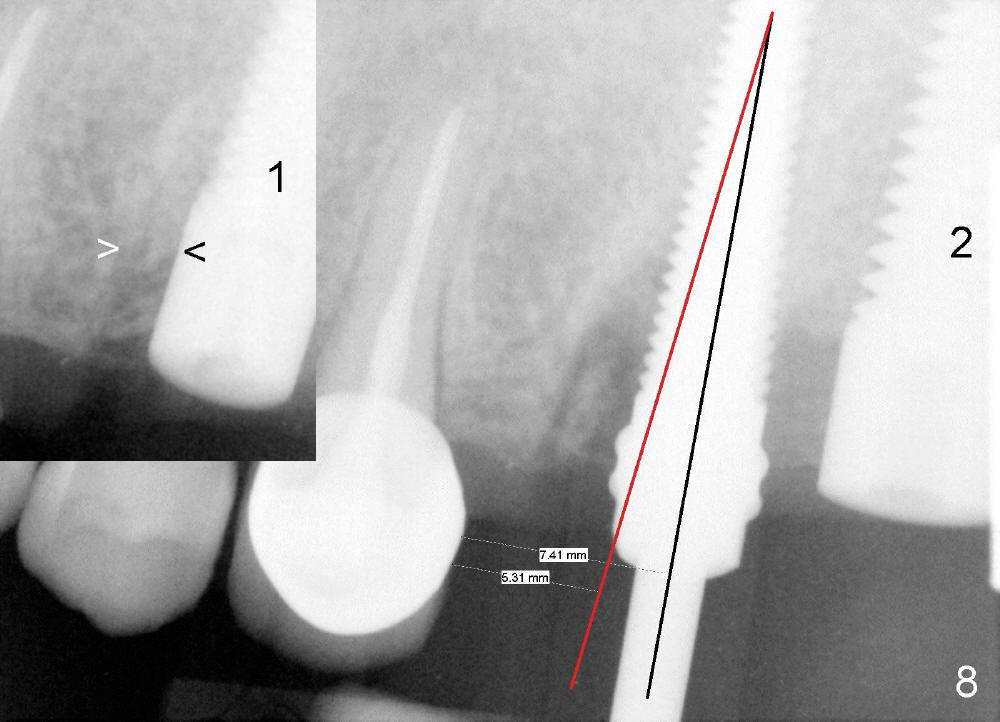

In fact, the implant at the 1st molar is planned to be placed 5.5 mm from the distal surface of the 2nd premolar (Fig.5). When the 1st intraop PA is taken with a 4.5x20 mm tap (Fig.6: T), the deviation is not noted (Fig.6: 7.5 mm vs. 5.5 mm in Fig.5). The trajectory of the implant (5x20 mm) remains deviated (Fig.7).

The trajectory should be corrected as early as possible and by changing the direction (Fig.8: from black line to red one). It should be not so difficult because of soft bone in the posterior maxilla and the mesiobuccal socket space (Fig.6 between arrowheads). It should be not too late to change the trajectory of an implant just placed.